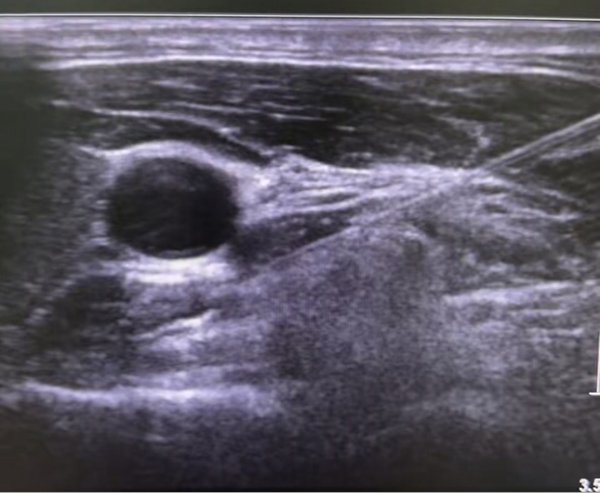

星状神经节阻滞(SGB),是在超声实时引导下使用超细穿刺针将少量的局麻药(如利多卡因)精准注射到星状神经节周围,调节交感神经,暂时“关闭”异常信号的传导,让紊乱的交感神经重归平衡,同时促使头面部血管扩张,消除脑血管痉挛,减轻肌肉挛缩,改善脑局部缺血缺氧,减少炎性介质释放,通过下丘脑机制调节机体的自主神经系统、内分泌系统和免疫系统的功能活动,有助于维持机体内环境的稳定。简单说,这就是一种精准的“开关调节”技术。

*优势:借助超声影像,医生能清晰看到颈部的颈动脉、甲状腺、神经节等重要结构,实现“看得见、避得开、打得准”的精准注射。